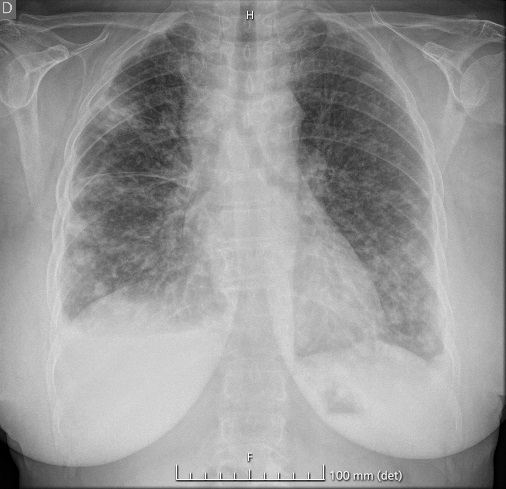

Se solicitó analítica, destacando aumento de reactantes de fase aguda, elevación de dímero D y alcalosis respiratoria. En la radiografía de tórax se identificó ensanchamiento mediastínico y nódulos bilaterales. Se realizó TC de tórax, con hallazgos de masa pulmonar en lóbulo superior derecho y múltiples adenopatías, constituyendo en mediastino anterior un conglomerado con severa compresión extrínseca de la vena cava superior.

El SVCS obedece mayoritariamente a una neoplasia subyacente, con el cáncer de pulmón como causa principal. La sospecha clínica se basa en síntomas como disnea y signos como el edema en esclavina y la circulación colateral en tórax. La radiografía de tórax muestra alteraciones hasta en el 85% de los casos, siendo clave en el diagnóstico inicial. La detección desde Urgencias permite instaurar un tratamiento precoz, mejorando la calidad de vida de los pacientes y la supervivencia.